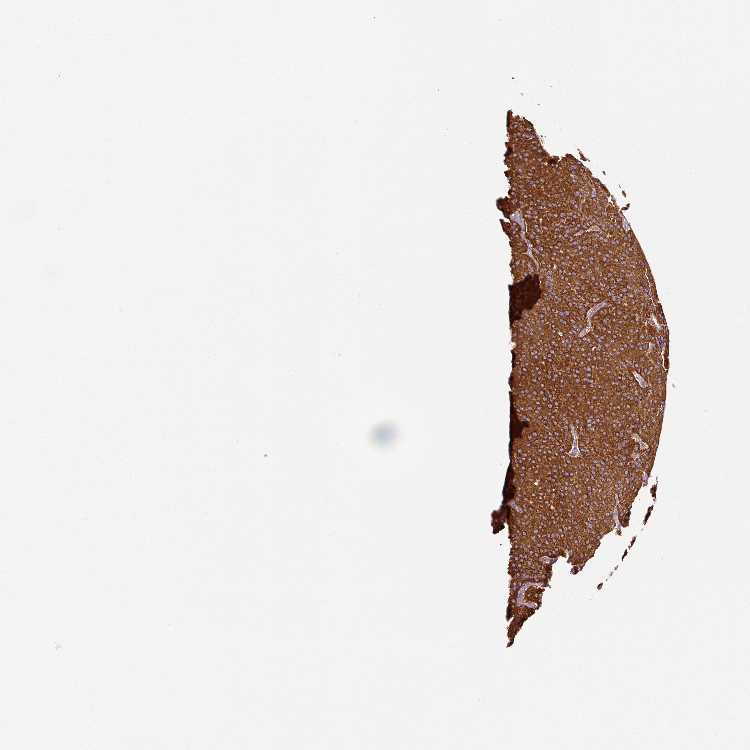

TISSUE PRIMARY DATA PARATHYROID GLAND Show tissue menu

PARATHYROID GLAND - Antibody stainingi

Antibody staining in the annotated cell types in the current human tissue is reported as not detected, low, medium, or high, based on conventional immunohistochemistry profiling in selected tissues. This score is based on the combination of the staining intensity and fraction of stained cells.

Each image is clickable and will lead to virtual microscopy that enables deeper exploration of all samples and also displays staining intensity scores, fraction scores and subcellular localization as well as patient and tissue information for each sample.

Antibody HPA041981Antibody CAB034929

Glandular cells HighMedium